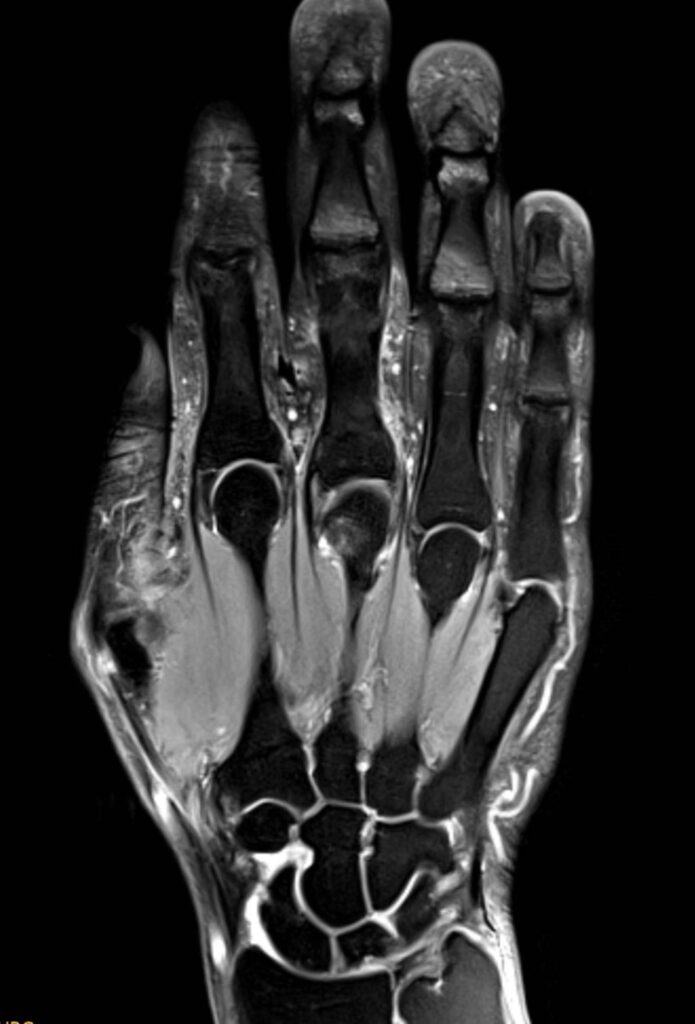

Was sieht man bei einer MRT der Hand?

Eine MRT der Hand liefert detaillierte Bilder aller vorhandenen Strukturen, darunter Knochen, Knorpel, Muskeln, Sehnen, Bänder und Nerven. Eine Hand MRT ermöglicht das Erkennen von Entzündungen, Schwellungen, Flüssigkeitsansammlungen, Rissen und anderen strukturellen Veränderungen und ermöglicht durch hochwertige Bildauflösung eine präzise Diagnose.

MRT Hand Bilder